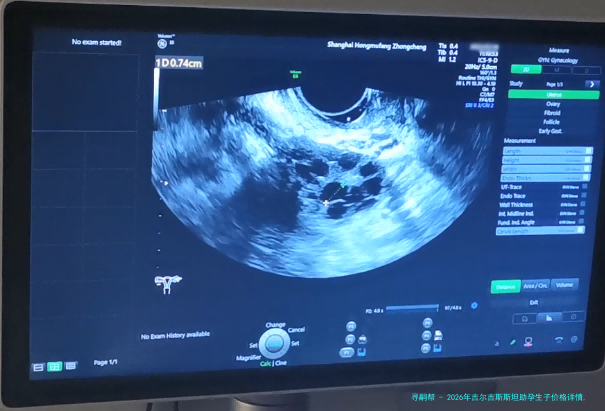

促排卵手术费用:医生会在B超引导下,通过阴道穿刺取出卵子。促排卵手术费用大概在800美圆至1500美金之间。